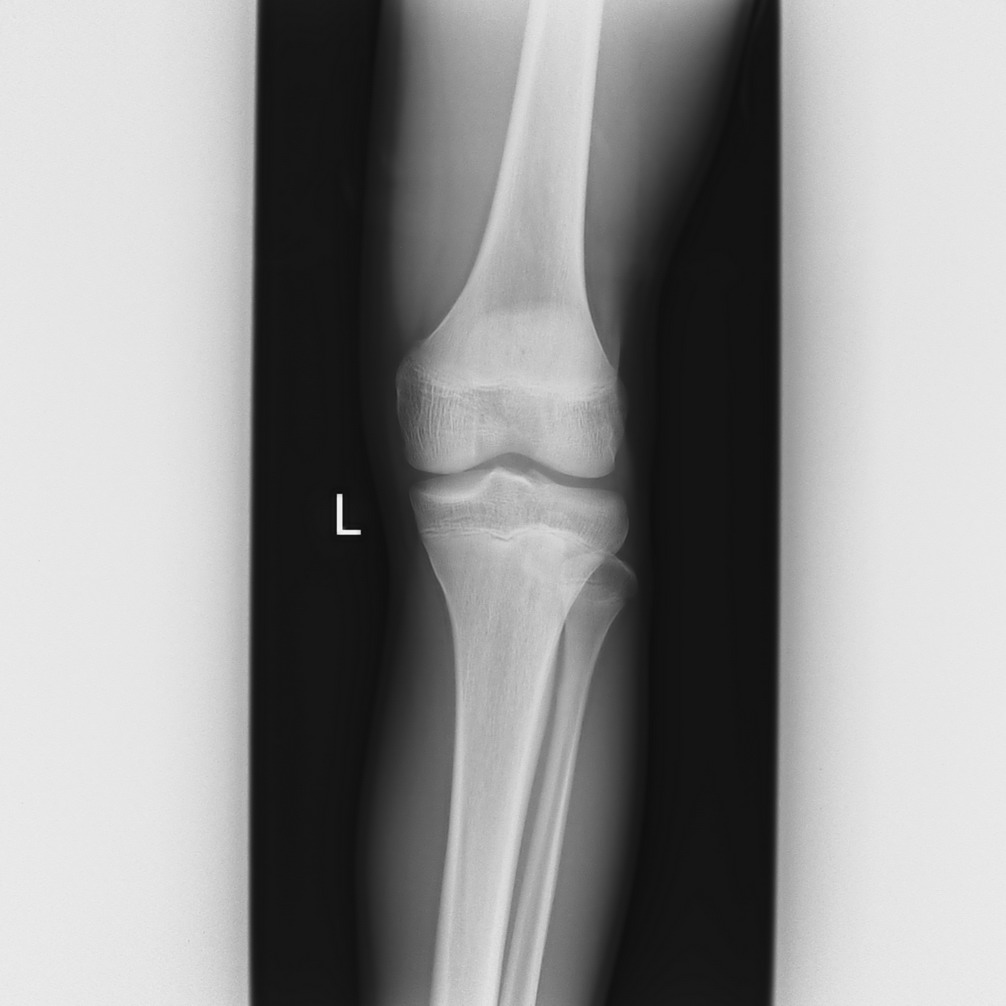

以下是引用qc80012345在2008-5-3 18:26:00的发言:[br]胫前结节缺血性骨软骨炎。

以下是引用宇宙ct在2008-5-3 19:16:00的发言:[br]胫前结节缺血性骨软骨炎